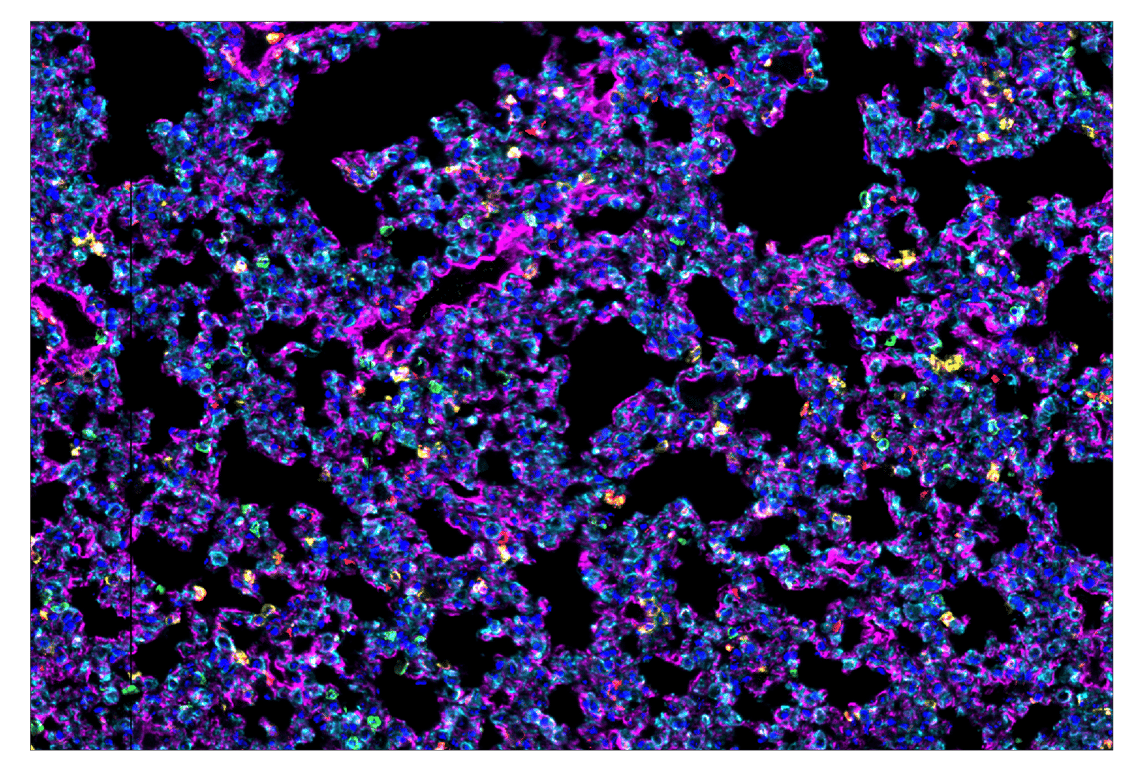

CD39/NTPDase 1 (E2X6B) & CO-0076-488 SignalStar Oligo-Antibody Pair #56428

SignalStar multiplex immunohistochemistry (IHC) is an advanced technology for labeling multiple proteins simultaneously in tissue samples using specific primary antibodies and fluorescent detection reagents. This technology offers accuracy and reliability in visualizing and analyzing protein expression while maintaining spatial context and tissue architecture.

SignalStar Oligo-Antibody Pairs are compatible with the SignalStar Multiplex IHC Buffer Kits for use in fluorescent multiplex imaging experiments. This product includes the oligo-conjugated antibodies and complementary oligos required for labeling your target protein on up to 10 slides. SignalStar Multiplex IHC Buffer Kits are required to amplify and image the target signal. Multiple oligo-antibody pairs can be conveniently combined into a multiplex panel using the SignalStar Multiplex IHC Panel Builder. SignalStar Multiplex IHC Kits & Reagents are not compatible with all of Cell Signaling Technology® products and protocols that are recommended for use in immunohistochemical assays.

CD39/NTPDase 1 (E2X6B) Rabbit Monoclonal Antibody (SignalStar™ Conjugate 0076) recognizes endogenous levels of total NTPDase 1 protein.